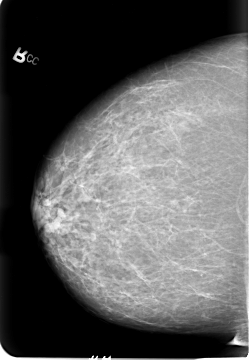

B_3021_1.LEFT_CC

FILE: B_3021_1.LEFT_CC.OVERLAY

TOTAL_ABNORMALITIES 3

ABNORMALITY 1

LESION_TYPE MASS SHAPE LOBULATED MARGINS CIRCUMSCRIBED-ILL_DEFINED

ASSESSMENT 3

SUBTLETY 3

PATHOLOGY MALIGNANT

TOTAL_OUTLINES 1

ABNORMALITY 2

ABNORMALITY 3